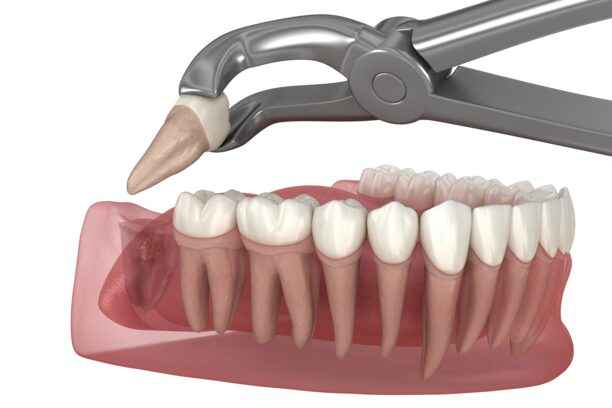

يُتخذ قرار خلع ضرس العقل عندما تتحول اعراض ضرس العقل من حالة عابرة إلى مشكلة مستمرة تؤثر على الصحة الفموية أو العامة. عادةً ما يُنصح بالخلع في حال تكرار الالتهابات أو فشل العلاجات التحفظية في السيطرة على الألم. كما أن استمرار اعراض ضرس العقل لفترات طويلة قد يؤدي إلى تآكل الأسنان المجاورة أو تشكل خراجات مؤلمة.

في أي الحالات يتم خلع ضرس العقل؟

توجد حالات محددة يصبح فيها خلع ضرس العقل خيارًا ضروريًا، ومنها:

• بزوغ الضرس بشكل مائل أو أفقي يضغط على الأسنان المجاورة.

كيف يتم إجراء جراحة ضرس العقل؟

تُعد جراحة ضرس العقل إجراءً طبيًا دقيقًا يُجرى عندما يفشل الضرس في البزوغ بشكل طبيعي أو يتسبب في آلام ومضاعفات مستمرة.

1. تبدأ العملية عادةً بتقييم شامل لحالة الفم باستخدام الأشعة السينية لتحديد موضع الضرس واتجاهه وعمق جذوره.

2. بعد ذلك يتم تخدير المنطقة تخديرًا موضعيًا، وقد يُلجأ إلى التخدير الكلي في الحالات المعقدة أو عند وجود أكثر من ضرس مطمور.

3. يقوم الطبيب بعمل شق جراحي بسيط في اللثة للوصول إلى الضرس، وقد يتم تقسيمه إلى أجزاء صغيرة لتسهيل إخراجه دون إلحاق ضرر بالأنسجة المجاورة.

4. بعد الانتهاء، تُنظف المنطقة بعناية وتُخاط اللثة بخيوط طبية قابلة للذوبان في أغلب الأحيان، لتبدأ مرحلة التعافي التدريجي.